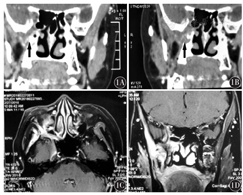

患者,女性,56岁,因右侧面部疼痛伴张口受限3年于2017年7月入我院。3年前无明显诱因自感右侧面部阵发性疼痛,可放射至同侧头部及眼眶,用力张口及咬合时疼痛明显加重,偶有右侧面部麻木感,无溢泪流涕、口角歪斜、闭眼乏力等不适。平时体健。当时外院拟诊为右侧颞下颌关节炎,给予抗感染及消炎镇痛药物治疗,自感疼痛减轻,但停药后反复加重,且渐感张口受限。于外院行右侧颞下颌关节磁共振成像(MRI)检查,未见明显异常。后来我院就诊,行鼻窦CT示:右侧翼腭窝间隙较对侧增宽(图1A、图1B),遂以"翼腭窝肿物"收住我院。患者住院后查体:张口受限,右侧面部肌力正常,鼻腔黏膜光滑,右侧颞下颌关节无明显压痛。进一步行翼腭窝增强MRI示:右侧蝶骨大翼、蝶骨体、上颌骨异常强化,考虑纤维骨化(图1C、图1D)。腮腺、颈部淋巴结、肝胆胰脾肾B型超声、胸部CT及颅脑CT检查均无明显异常。后全身麻醉下经鼻内镜右侧翼突径路翼腭窝间隙探查及肿瘤切除术,剪除部分中鼻甲开放上颌窦,磨除上颌窦后壁骨质及翼突根部,暴露翼腭窝间隙,显露上颌神经及翼管神经,见神经周围软组织包绕(图2A)。息肉钳咬取部分翼管神经周围软组织送快速冷冻病理示:可疑腺样囊性癌。进一步探查肿瘤累及翼内翼外肌,考虑到该肿瘤易沿神经血管走行,向患者家属交代病情及进一步手术风险后,根据患者家属意愿,应用鼻用动力系统及低温等离子射频消融清除可见癌灶及部分翼内外肌后停止手术。术后常规病理:光学显微镜下见肿瘤细胞成筛状、带状排列,筛网样结构内可见黏液样物质(图2B);免疫组织化学:CEA阳性,Ki-67阳性约10%,p40阴性,NSE阴性,SMA阳性,CK7阳性,符合腺样囊性癌。患者出院后外院行局部放疗(60 Gy),定期门诊复查1年,未见复发。

头颈部腺样囊性癌因原发部位较隐蔽,早期难以发现及确诊。肿瘤发展到一定程度,表现出破坏性及占位影响时,超声、X线及CT都是该病的有效影像学检查手段。本例患者就诊于我科时主诉为右侧面部疼痛伴张口受限3年,平时无鼻塞、流涕及嗅觉异常,在颞下颌关节CT和MRI已排除颞下颌关节情况下,不可忽略鼻窦、颅底病变。阅其鼻窦CT片时对比发现右侧翼腭窝间隙较左侧明显增宽,故进一步行翼腭窝增强MRI检查,见该区明显强化,考虑右侧翼腭窝间隙占位性病变。